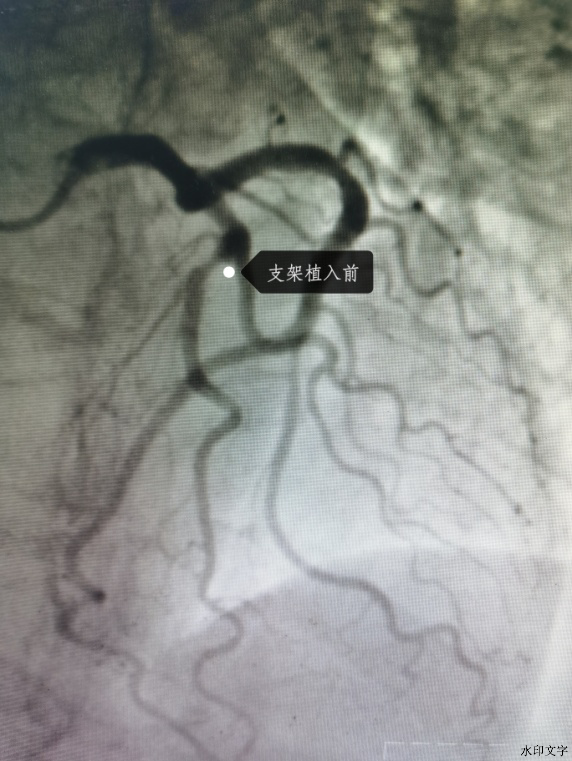

蔡先生1年前曾在我院冠脉CTA检查提示LAD近段轻度狭窄,日前胸闷症状仍有反复,在居住的当地动态心电图检查,捕捉到ST段动态性改变,为进一步诊疗于9月1日收住我院心内科。入院的第二天行冠脉造影发现前降支中段狭窄80%,并给予了IVUS检查,提示狭窄部位为脂质斑块,该斑块易发生炎症、破裂,一旦发展会导致血管的梗塞;且有效管腔面积 3.1mm2(MIN DIA .8MM MAXDIA 2.1MM 斑块负荷8.1mm2 72.1% EEM 11.2MM2 MIN DIA 3.5MM MAX DIA 4.2MM)。

根据IVUS的测出的血管管腔大小给予植入3.0*30mm药物洗脱支架,取3.25*12mm非顺应性球囊送至左前降支病变段支架内,在支架内以18-20atm扩张塑形。再次行IVUS检查证实支架贴壁良好。